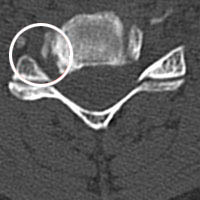

Die Computertomographie (abgekürzt CT) ist ein diagnostisches Verfahren, mit dem das Körperinnere genau abgebildet werden kann. Sie ist seit den 70er Jahren fester Bestandteil der medizinischen Diagnostik. Bei der Computertomographie werden in einer kurzen Röhre Querschnittsbilder des Körpers erzeugt. Während eines vollständigen Umlaufs der Röntgenröhre um den Körper werden fächerförmig Röntgenstrahlen durch den Körper geschickt und es wird die Abschwächung der Röntgenstrahlen hinter dem Patienten aufgezeichnet. Diese Informationen werden nach elektronischer Datenverarbeitung mittels Computer als Bild (Tomographie) dargestellt. Im Gegensatz zu den gewöhnlichen Röntgenuntersuchungen können die Organe überlagerungsfrei abgebildet und damit besser beurteilt werden. Die Computertomographie eignet sich für die Untersuchung von Schädel, Brust- und Bauchraum sowie Knochen.

Der Patient/die Patientin liegt bei der Untersuchung auf einem Tisch, der durch eine runde Öffnung bis zur Stelle die untersucht werden soll ins Gerät hineingeschoben wird. Von dieser Körperstelle aus werden zahlreiche Querschnittesbilder im Abstand von wenigen Millimetern gemacht, bis die zu untersuchende Körperregion abgetastet ist. Während der Aufnahme muss der Patient in der Regel den Atem anhalten, da sonst die Bilder durch die Atembewegung unscharf werden.